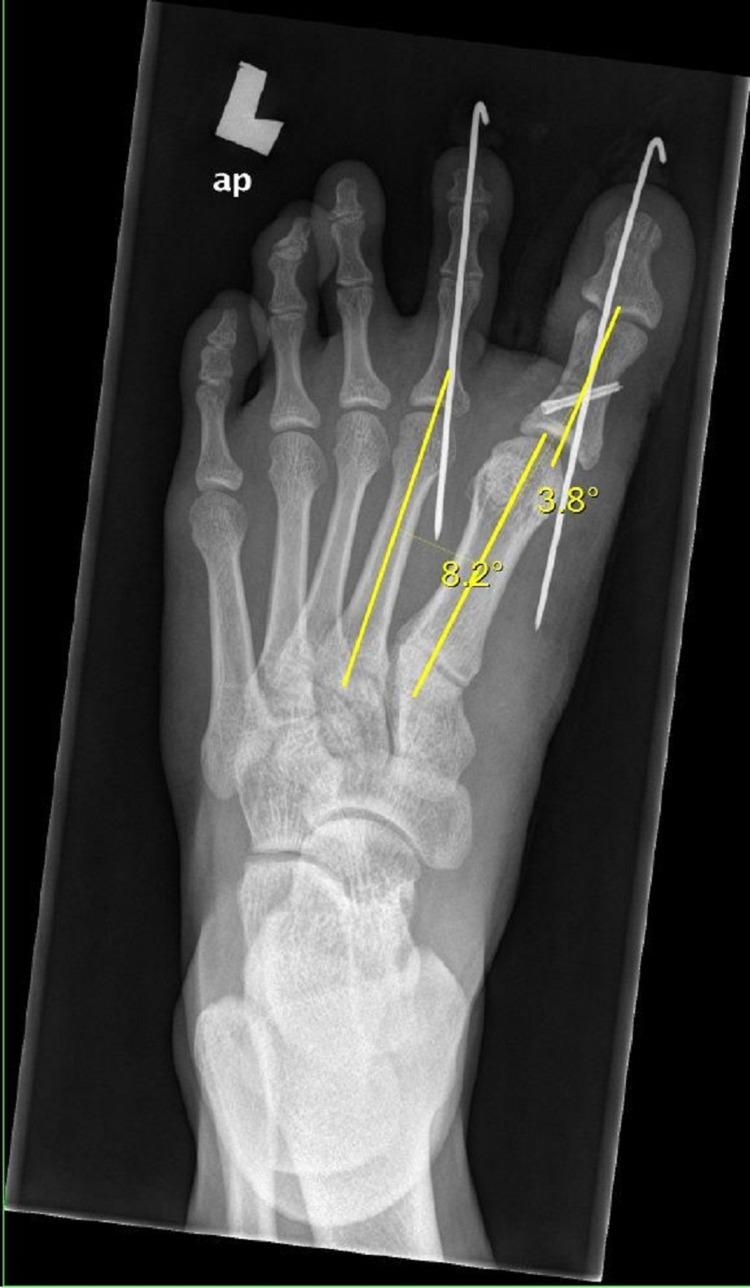

Congenital hallux varus is a rare forefoot deformity presenting with a deviation of the great toe medially. There are various techniques for the treatment of congenital hallux varus described in the literature. We present a case of a 16-year-old boy with congenital hallux varus who underwent corrective surgery, which involved soft tissue and bony procedure for better functional and clinical outcomes.

先天性拇内翻是一种罕见的前足畸形,表现为拇指向内侧偏斜。文献中描述了多种治疗先天性拇内翻的技术。我们报告一例16岁患有先天性拇内翻的男孩,他接受了矫正手术,该手术包括软组织和骨手术,以获得更好的功能和临床效果。